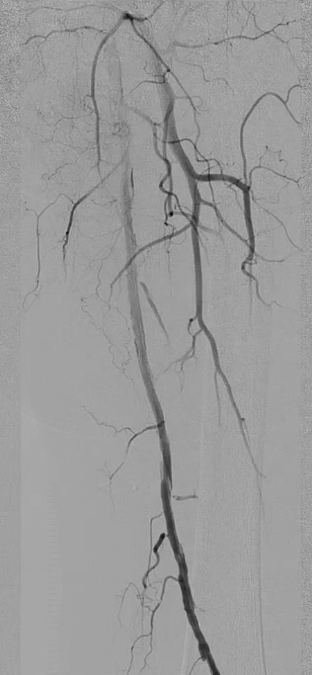

术中造影确认病变

左侧股浅动脉中上段明确长段狭窄并闭塞,病变长度约15cm,股浅动脉远段至腘动脉管腔通畅。

膝下动脉三支主干均闭塞,胫后动脉远端经侧支循环显影;腓动脉远端为“休眠血管”,通过与胫后动脉的交通支实现逆向显影。